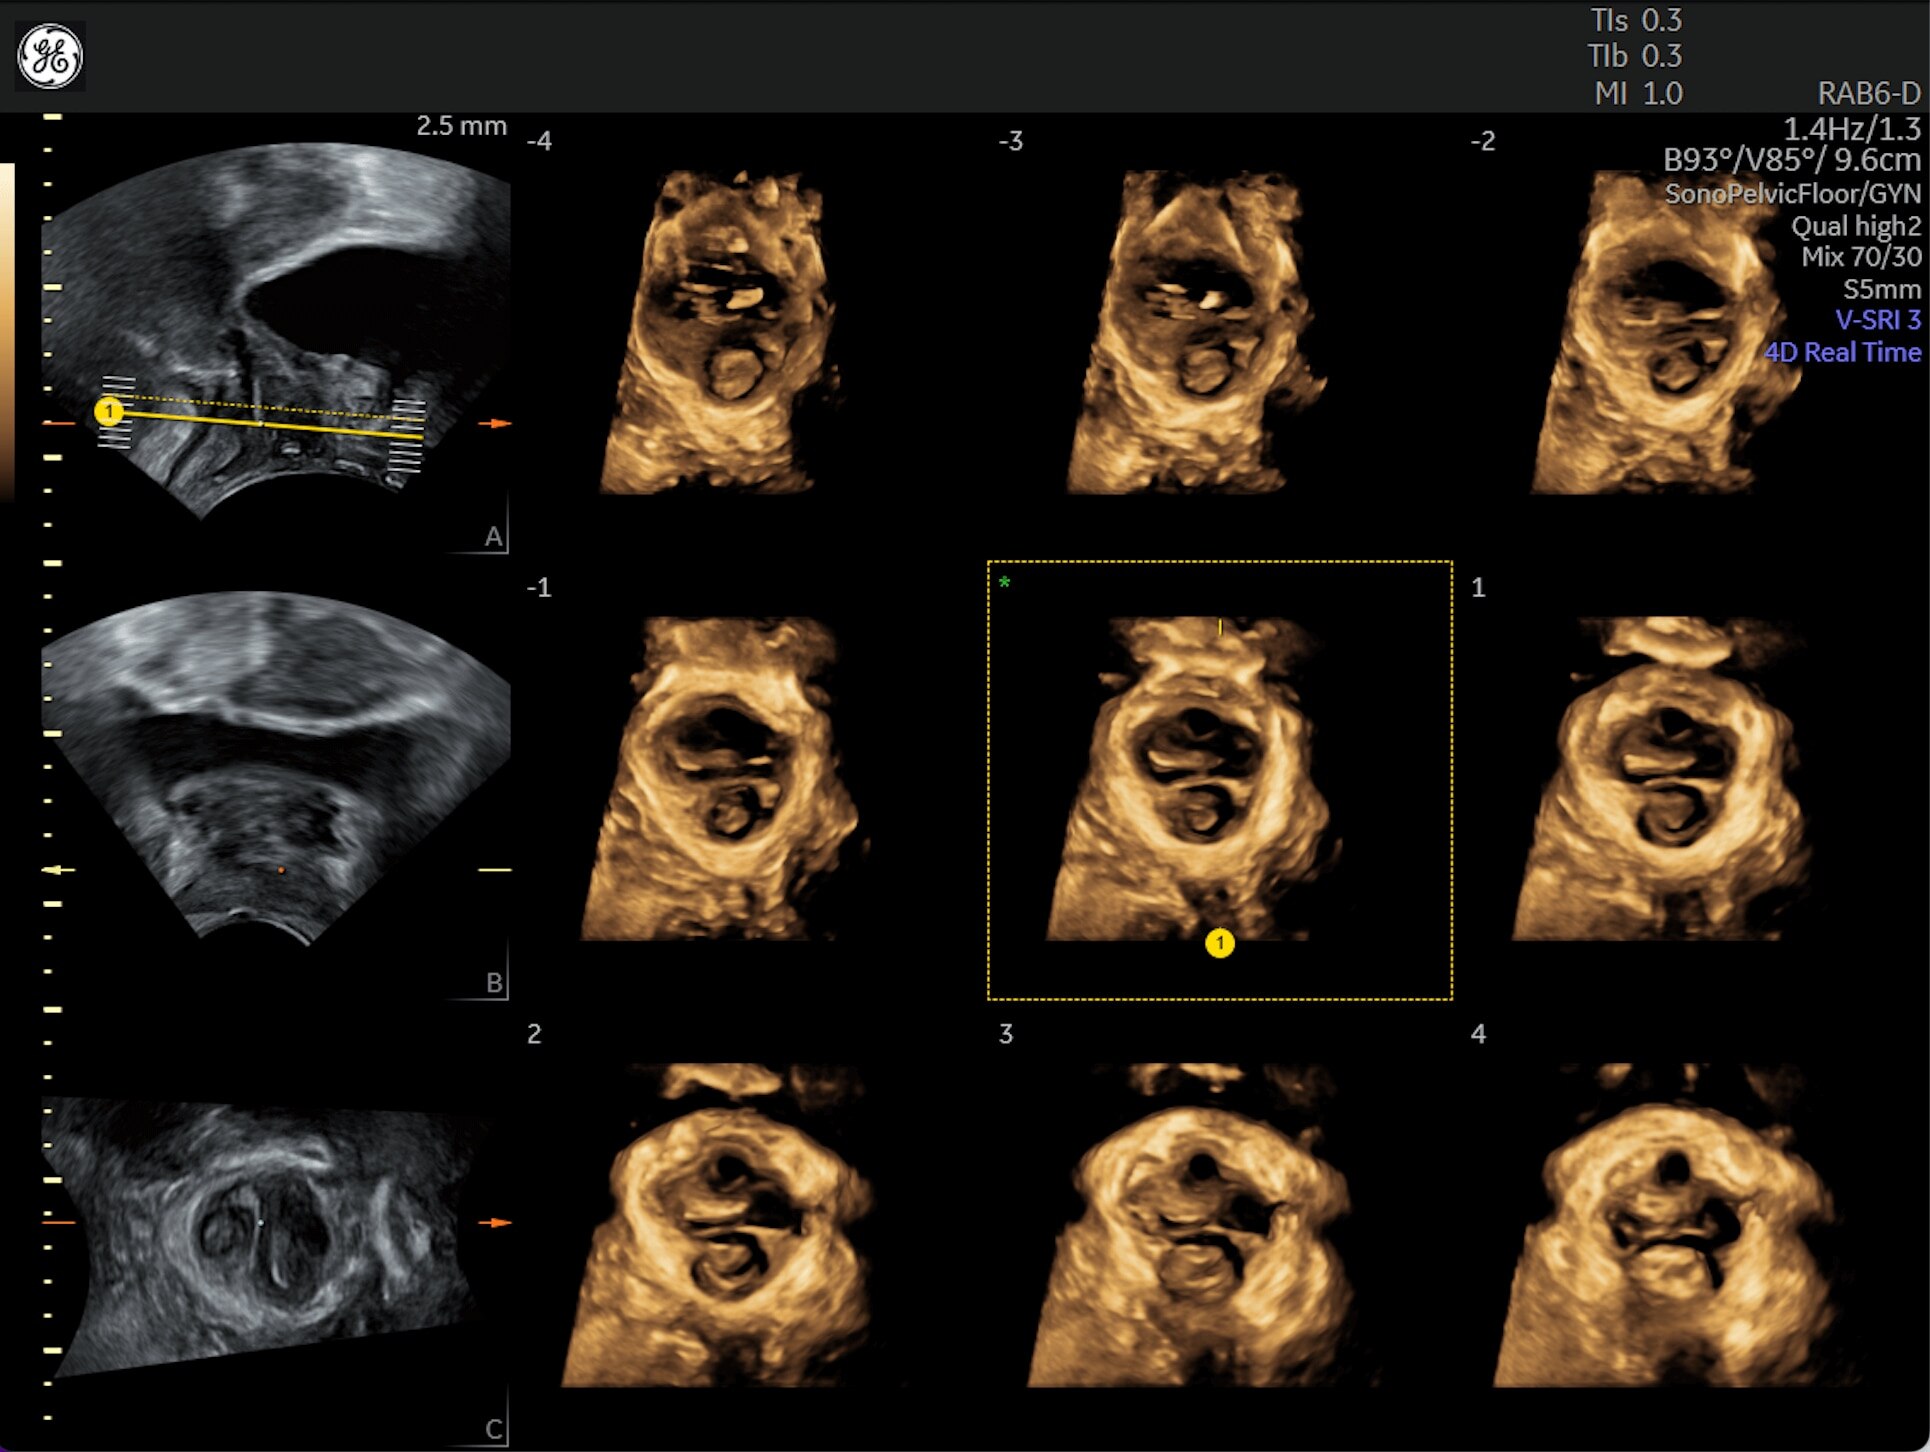

Generate spectacular 2D/3D and color Doppler images with increased penetration and stunning clarity, to help visualize critical details needed for diagnostic assurance. The Lyric Architecture unlocks new imaging and processing power to expand your imaging capabilities for years to come